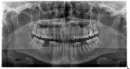

Был на приёме у стоматолога, и делали снимок. Снимок делали для другого, но когда врач изучал снимок, то увидел на переднем зубе воспаление. Врач сказал, что нужно удалять нервы, которые якобы уже умерли, все там чистить и пломбировать. Зуб меня не беспокоил и не беспокоит. 2 года назад ставили пломбу - болей не было. Интересующий зуб на снимке выделен красной точкой. Совсем не хочется нарваться на ошибку и залечить здоровый зуб.

По данному снимку, у верхушки корня 12 зуба есть очаг воспаления - хронический апикальный периодонтит. Скорее всего, ранее у вас был глубокий кариес и пломба стоит очень близко к пульповой камере. Поэтому пульпа зуба (нерв мертвый) в нем уже некротизированна. Следует провести эндодонтическое лечение зуба (удалить нерв, обработать корневой канал и запломбировать сначала временно с помощью лекарственного препарата на основе кальция, после постоянно), и восстановить коронковую часть зуба.